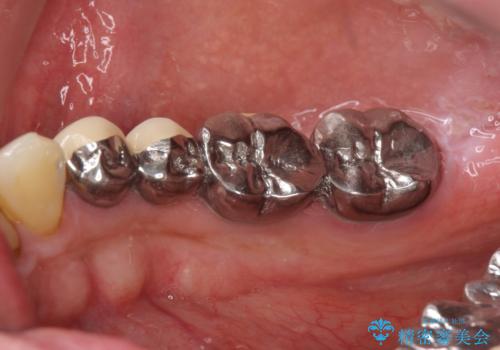

インプラント治療・セラミック治療を含む 全顎的虫歯治療

以上のような問題を、徹底的な虫歯治療、歯周外科、インプラント治療、部分矯正治療、精密根管治療を用いてひとつずつ解決ししっかりと長期的に食事を楽しめるような口腔内環境の再構築を目指します。